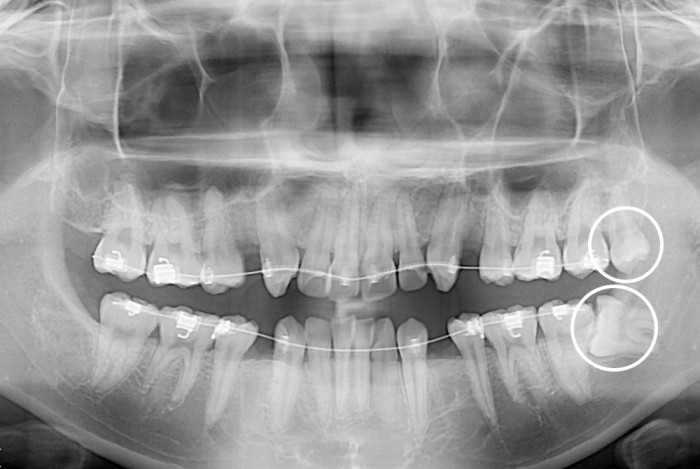

[사랑니] 사랑니

치료전 : 2019-06-19